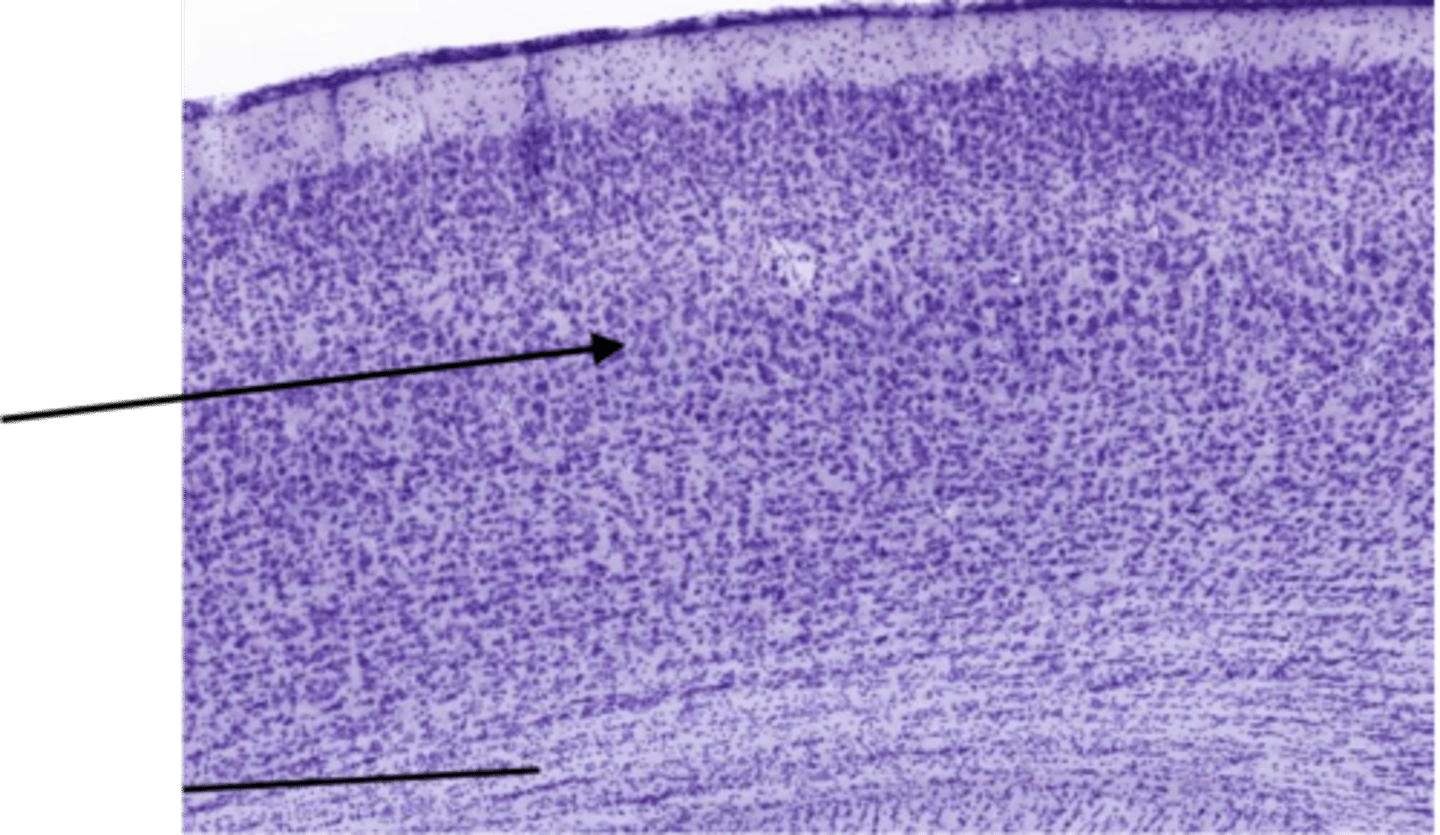

Identify the portion of the CNS

cerebellum

Identify the layer of the cerebellum

molecular layer

white matter

purkinje layer

pia mater

granular layer